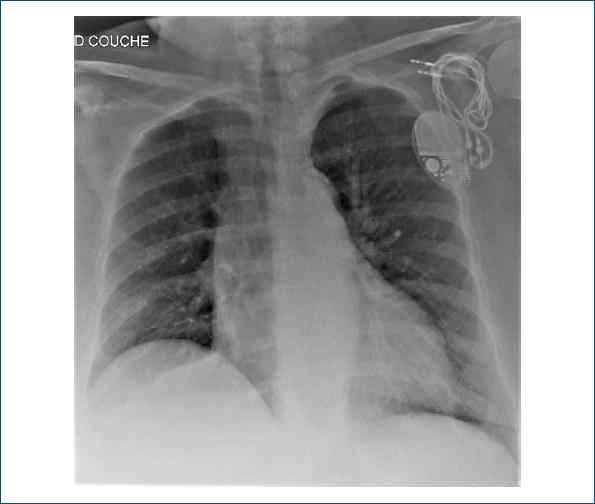

Figura 1 Radiografía de tórax de la paciente. Obsérvense en la región subclavicular izquierda los cables del marcapasos completamente fuera del corazón. D: derecha; couche: acostado en francés.

La figura 1 pertenece a una paciente de 77 años con antecedentes de trastornos psiquiátricos y neurocognitivos, múltiples consultas al servicio de urgencias e internaciones por causas sociales más que médicas. A ellos se suma la colocación de un marcapasos en marzo de 2018 por bradicardia en el contexto de un bloqueo auriculoventricular 2:1. En enero de 2019 la paciente es hospitalizada por debilidad general luego de un cuadro gastrointestinal; el ECG revela fibrilación auricular y signos de disfunción de sensado y captura del marcapasos de doble cámara, con espigas de marcapasos disociadas del ritmo de base del paciente (Fig. 2). Como puede observarse en la figura 1, la paciente muestra un desplazamiento de los cables del marcapasos, confirmado por ella misma, secundario a múltiples rotaciones sobre su eje por manipulación externa de éste, una alteración que se conoce como síndrome de twiddler 1,2. Se le implanta un nuevo marcapasos al poco tiempo y la paciente recibe el alta (Fig. 3).